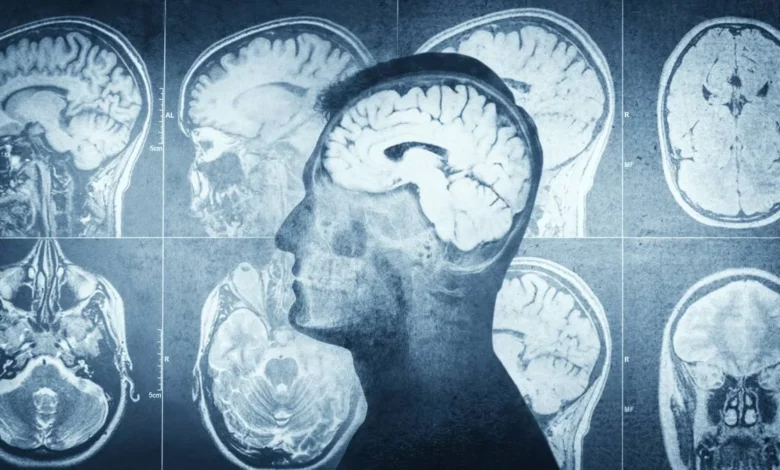

San Pedro Sula.- En un avance histórico para la medicina en Honduras, se ha creado el primer protocolo nacional para tratar infartos cerebrales. Esta iniciativa, impulsada desde el Hospital Mario Catarino Rivas, tiene como objetivo estandarizar la atención médica y reducir drásticamente las tasas de mortalidad y discapacidad causadas por los ataques cerebrovasculares (ACV) en el país.

La nueva guía médica busca optimizar cada minuto desde que el paciente presenta los primeros síntomas hasta que recibe tratamiento especializado. Según el doctor Javier Lagos Servellón, neurólogo intervencionista y uno de los promotores del proyecto, el protocolo establece:

El protocolo enfatiza que el tiempo es un factor crítico, ya que cada minuto sin irrigación sanguínea en el cerebro resulta en la pérdida de millones de neuronas. Se insta a la población a buscar ayuda médica inmediata si se presentan señales como: